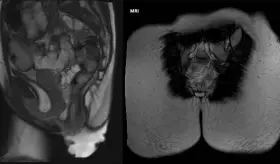

Experto en cirugía robótica urológica explica cómo funciona el procedimiento, en qué ocasiones se utiliza y las ventajas que ofrece al paciente.

¿Cuándo es realmente necesario una cirugía robótica en urología?

Las técnicas laparoscópicas han revolucionado la cirugía de cáncer de próstata, mejorando la recuperación y calidad de vida de los pacientes.